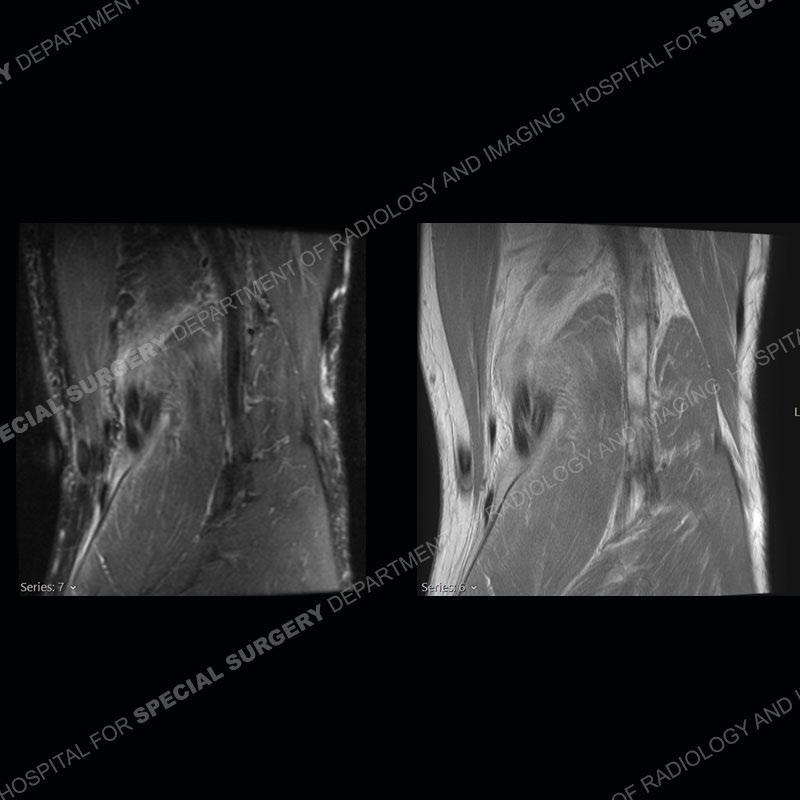

The radiographs show degenerative change of the medial compartment and a varus knee, but they are not germane to this case. No acute bony injury is present. The MRI shows edema of the posterior medial knee/soft tissue and a focal area of a partially disrupted low signal structure. The details are kept at a minimum in the findings of this case on purpose.

The findings were kept purposefully vague as identifying the structures early on takes away a lot of the diagnosis. An uncommon entity and one of which we do not see a lot. Enthesopathic changes and tendinosis are seen as are distal MHG injuries, but proximal tears are rarely present. This case highlights a number of points. One, it almost always comes down to anatomy. Perhaps not a structure we normally spend too much time on, except save for diagnosing a Baker’s cyst, but knowing where this structure and all structures exist in all three planes is imperative. Second, when you think you are making a “call” or finding that you have never made before, step back and think is this just the abnormal presentation of a common pathology. That situation arises much more frequently. Third, if you look at it once, twice, and probably a third time and are confident in your odd or very rare diagnosis, stick to your guns. Especially, when it comes down to anatomic structures, the proof will be in the images.

Fourth, use all imaging planes and different pulse sequences to make your diagnosis. The edema highlighted in this case can be seen as the obscuration of fat on the PD images but is much easier to perceive as the high signal on the IR pulse sequences. The actual disruption of the MHG myotendinous junction is only able to be seen on the axial images. On the sagittal and coronal images, we get a sense something is wrong but hard to be exact. Lastly, when you look at a study and something just seems off (as I would say the sagittal and coronal images do with that dark band of tissue posteriorly), listen to yourself and go through the study slowly and meticulously. Most of the time you will find you were right, and something indeed is present.